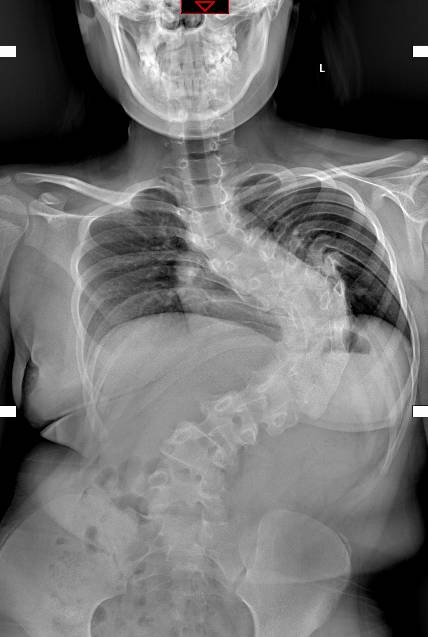

15岁女孩朱小慧(化名),在1岁多刚学走路时被家人发现脊柱侧弯,至今已有近14年,脊柱侧弯已进展到了140度,如今15岁的她身高只有135cm,而且脊柱侧弯已经压迫到内脏,并出现活动后气短,心悸等情况。据小慧的母亲讲,因为身体的缺陷,小慧变得性格孤僻,经常独来独往,从来不跟同龄的小伙伴玩耍。因此,挺直腰板一直是小慧的梦想。

精心的准备得到了回报:经过三周的牵引,11月25日上午,患者小慧被推进手术室。由周献伟率领的脊柱外科团队凭借充分的术前准备和精湛的手术技艺,为小慧成功实施了胸椎后路全脊柱360°截骨、矫形植骨融合钉棒内固定术。术后小慧恢复很快,神经功能无损伤,矫形效果满意。术后患者转往重症医学科,术后第一天患者生命体征平稳,四肢活动量灵活,标志着此次手术的完全成功。现在小慧身体各项指标逐渐恢复正常,马上就可以下床了,背部较术前平坦了许多,身高也增加到了146cm。